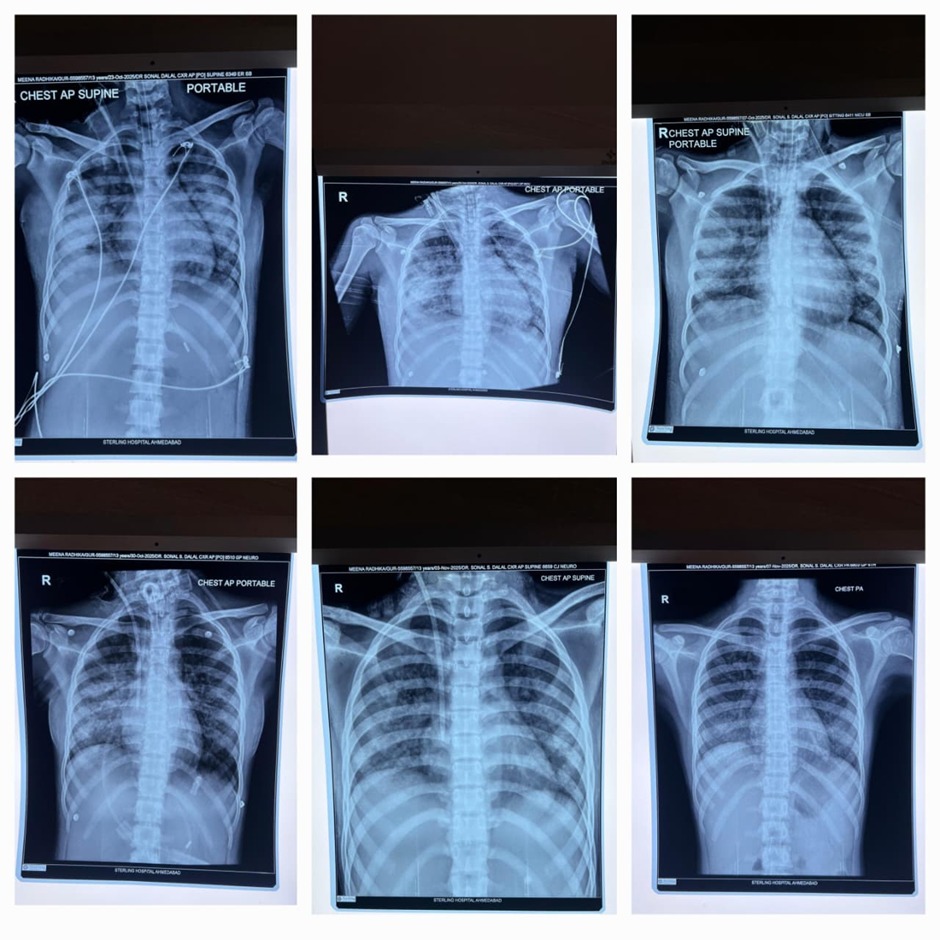

She was diagnosed with falciparum malaria that had caused acute kidney injury, lung damage, and multi-organ complications. Under the expert care of Dr. Sonal Dalal and Dr. Amrish Patel (Pulmonologist & Critical Care Specialist), the ICU team initiated rapid, advanced treatment, including dialysis and specialized critical care support. She remained on a ventilator for 12 days and showed steady improvement with round-the-clock monitoring.

Sterling Hospital, Ahmedabad’s Dr. Amrish Patel (Pulmonologist & Critical Care Specialist) explained that when the patient arrived, her oxygen levels were dangerously low, and she was struggling to breathe. She had been shifted from Rajasthan on ventilator support due to her fragile condition. The team immediately initiated specialized treatment to stabilize her. She was diagnosed with falciparum malaria, which had led to kidney damage, lung complications, and multi-organ involvement. After dialysis and medical management, she remained on ventilator support for 12 days, during which her life was saved through advanced care administered by the critical care team.

Dr. Amrish Patel (Pulmonologist & Critical Care Specialist) added that a bronchoscopy was performed to clear the secretions from her lungs. an essential step that further contributed to her recovery. As her condition improved, the ventilator support was gradually removed, and she was shifted to a normal room. By then, she had entered the recovery phase. After approximately 18 days of treatment, her life was saved through advanced care, and she was discharged in a stable and healthy condition.